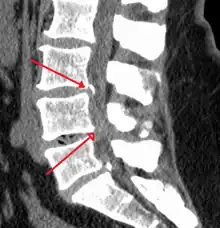

On parle de sténose foraminale lorsque le foramen intervertébral se rétrécit à la suite de l’effondrement d’un disque. Les nerfs rachidiens sortent du canal rachidien entre les vertèbres en empruntant un tunnel appelé foramen intervertébral. La perte de hauteur induite entraîne l’affaissement de la vertèbre au-dessus du disque vers celle située en dessous : l’ouverture entre les deux vertèbres se rétrécit jusqu’à comprimer le nerf.

Le phénomène d’arthrose au niveau des facettes articulaires engendre la formation d’ostéophytes qui vont tendre vers le foramen, causant ainsi une compression supplémentaire et une irritation. La sténose foraminale peut entraîner une « double douleur », mécanique et neurologique provenant de l’irritation de la racine nerveuse.